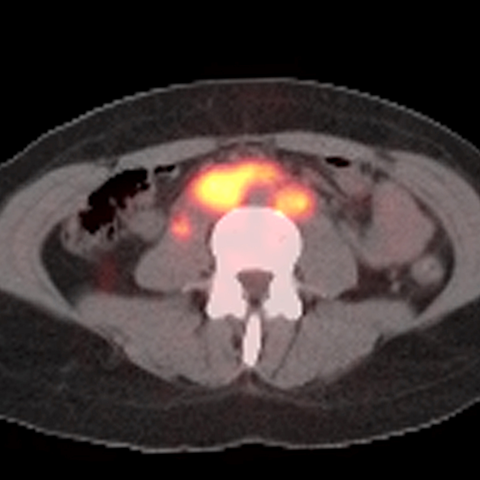

40 year old male presents with lymphadenopathy and unexpected weight loss [1 of 4]